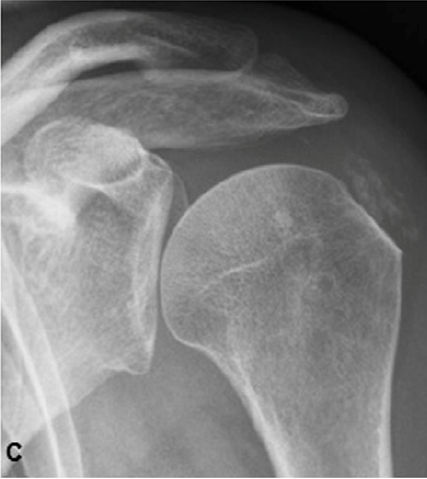

Ακτινολογική ταξινόμηση της ασβεστοποίησης στον ώμο (Gartner and Hayer)

Ανάλογα με την απεικόνιση στην ακτινογραφία ταξινομείτε ως εξής:

| Τύπος Ι : Ομαλά όρια, αυξημένη πυκνότητα ασβέστωσης. Φάση σχηματισμού | Τύπος ΙΙ: Σχήμα ομαλό, πυκνό ή οξύ, περιοχές ακτινοδιαπερατές. Φάση σταθεροποποίησης | Τύπος ΙΙΙ: Διάφανη, νεφελώδης εμφάνιση, χωρίς σαφή όρια. Φάση απορρόφησης |